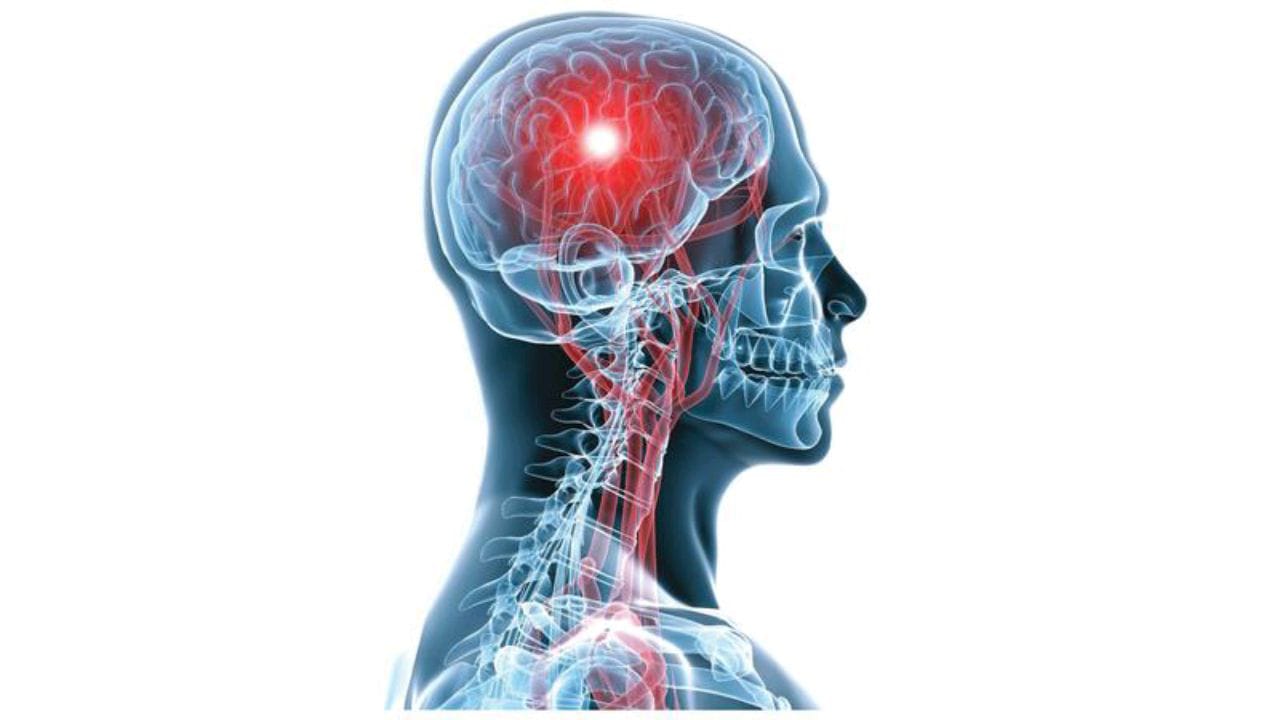

أعراض تمدد الأوعية الدموية الدماغي وعوامل خطورته